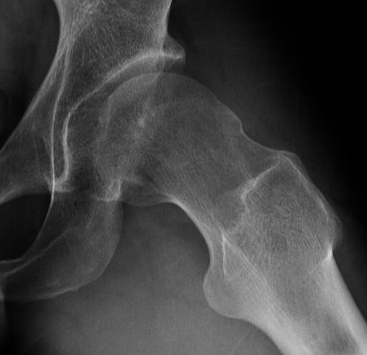

Osteoarthritis

Tonnis Grade

| Grade 0 | No sign of arthritis |

| Grade 1 | Sclerosis, slight narrowing of joint space |

| Grade 2 | Cyst, moderate narrowing of joint space, loss sphericity of femoral head |

| Grade 3 | Severe narrowing or obliteration of joint space |

Tonnis grade 0 Tonnis grade 1 Tonnis grade 1